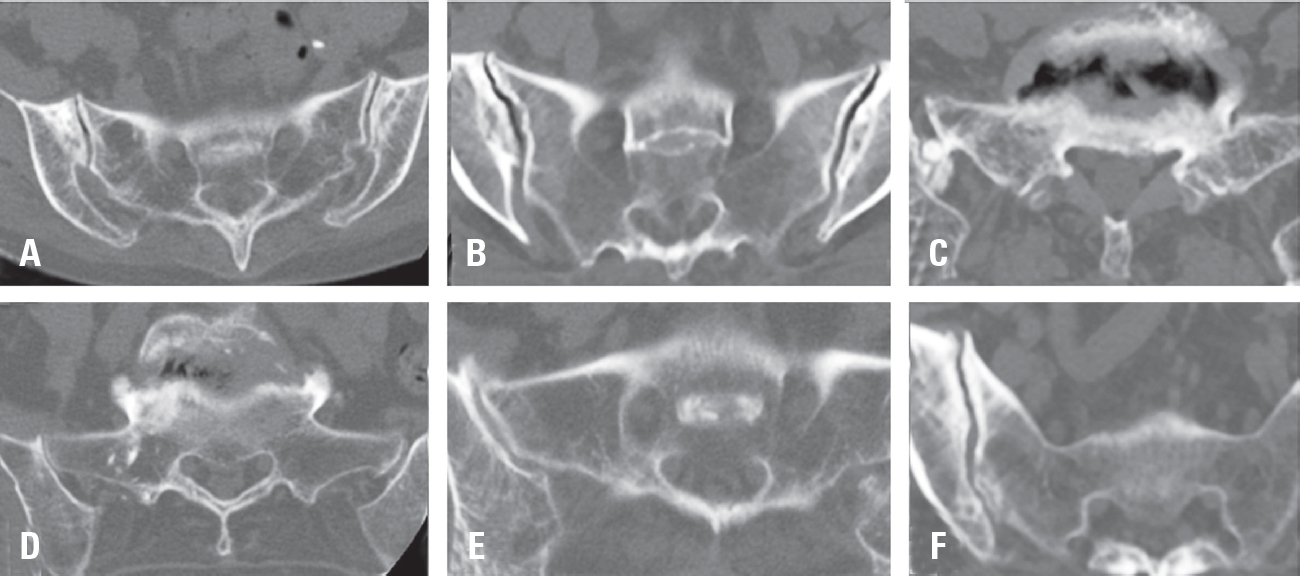

2. Radiological criteria and diagnosis of sacroiliac joint degeneration

CT scans were performed both preoperatively and 6 months postoperatively to evaluate radiological changes in the sacroiliac joint. The relatively short follow-up period minimized the potential bias from age-related degenerative changes. The radiological assessment of degenerative changes in the sacroiliac joint was based on seven factors: sclerotic changes, erosion, osteophyte formation, intra-articular bone formation, joint space narrowing, intra-articular gas formation, and subchondral cysts (Fig. 1). Postoperative degeneration of the sacroiliac joint was diagnosed if one or more of these CT findings were present. Each of the seven factors was assigned a score: 1 point for unilateral presence, 2 points for bilateral presence, and 0 points for absence. The total score, which could range up to 14 points, was treated as a continuous variable. If the change in the continuous score was 2 points or more at the 6-month CT scan, the patient was diagnosed with postoperative sacroiliac joint degeneration.12-17)

Fig. 1.

Evaluation factors for radiographic degeneration. Bone cyst (A). Bone erosion and intra-articular gas formation (B). Intra-articular bone formation (C). Joint space narrowing (D). Osteophyte (E). Sclerotic change (F).